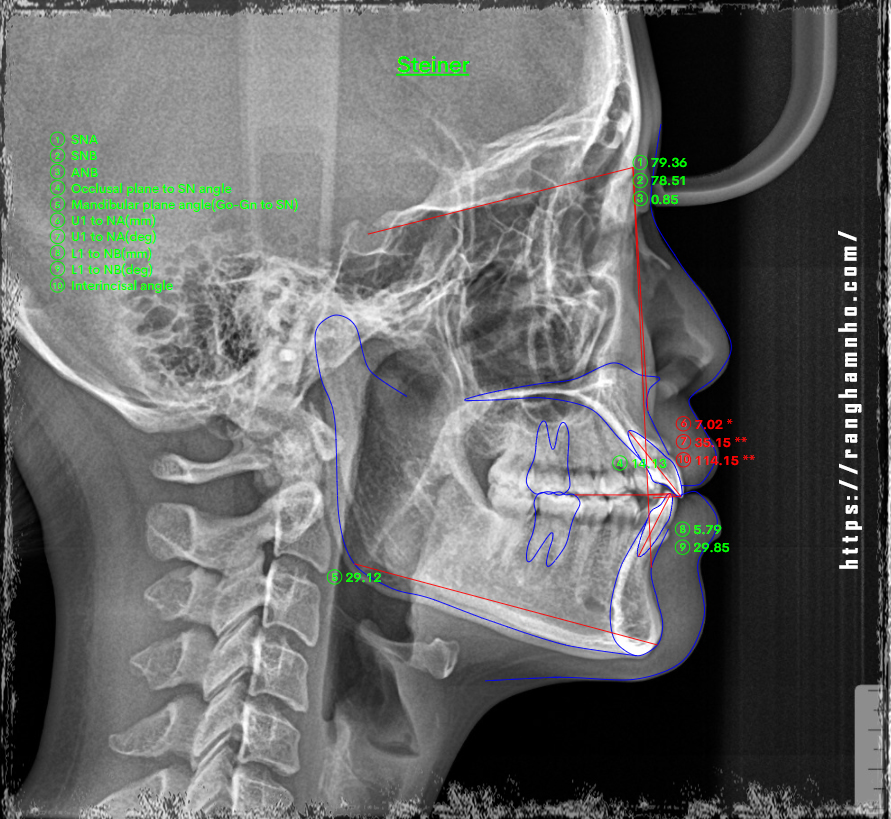

BN chọn niềng mắc cài thẩm mỹ tự buộc- saphirre tự buộc của mỹ, kết quả sau 1.5 năm niềng được tháo với nụ cười và khuôn mặt thay đổi nhiều sau niềng.